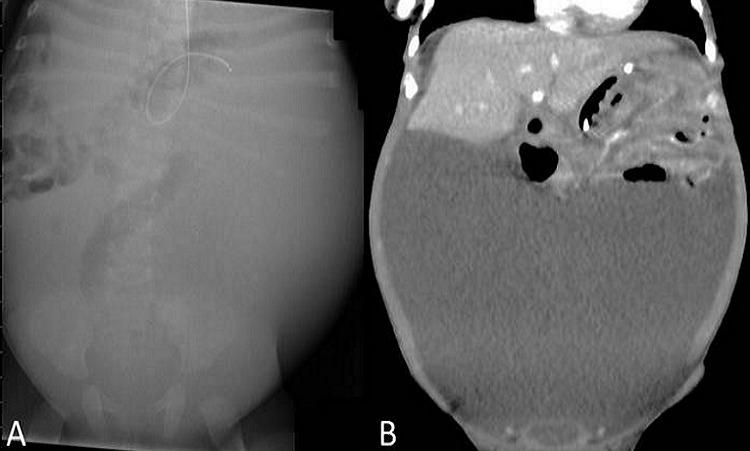

Angiomyxoma in Accessory Hepatic Lobe.

APSP J Case Rep. 2016 Jan 1;7(1):10. eCollection 2016 Jan-Apr.

https://cdn.ncbi.nlm.nih.gov/pmc/blobs/ac9b/4715883/315a34498112/ajcr-7-10.f1.jpg